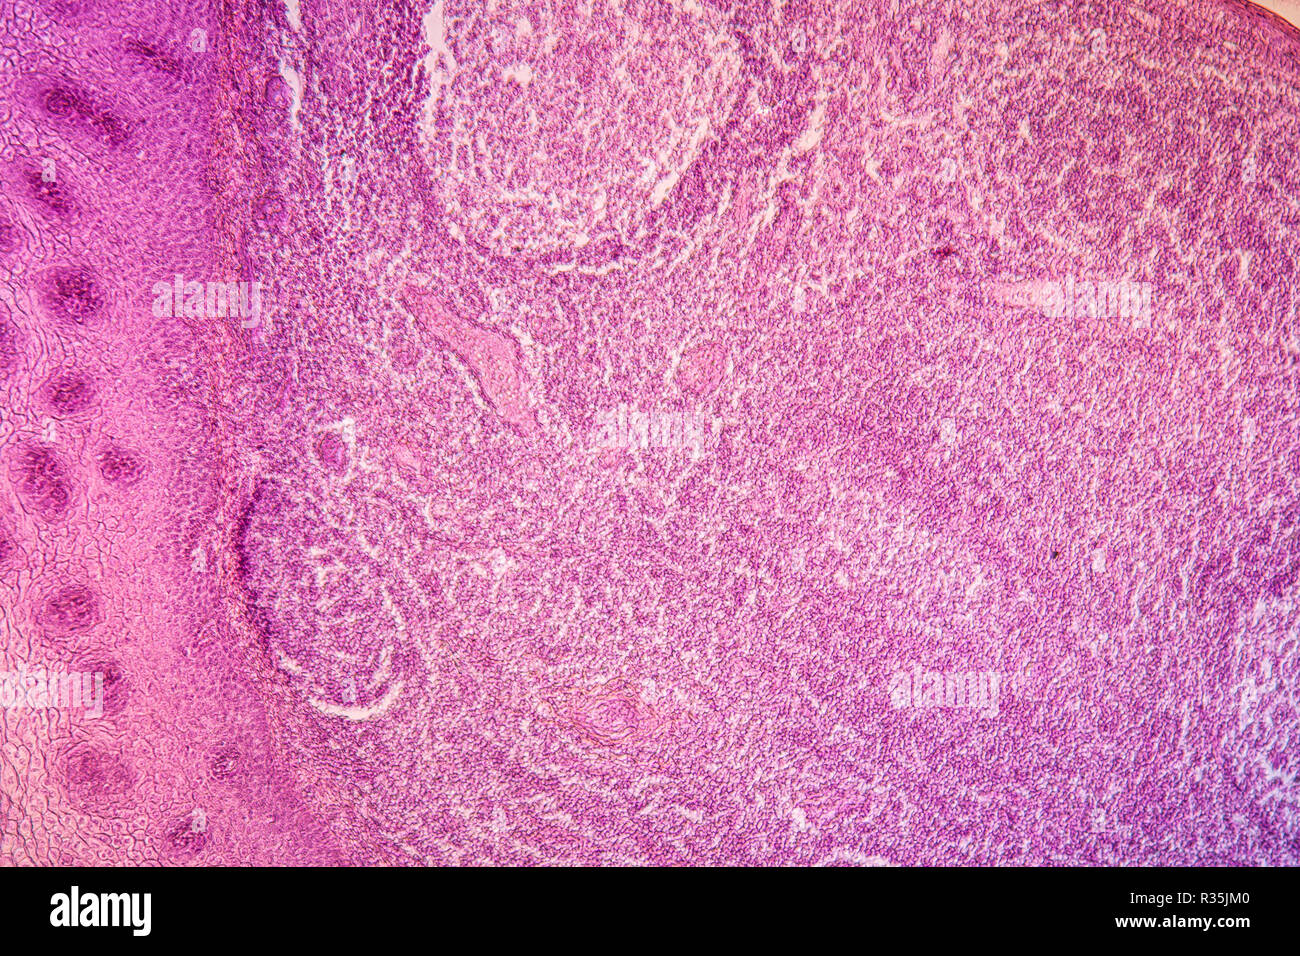

Mandelentzündung Stockfotohttps://www.alamy.de/image-license-details/?v=1https://www.alamy.de/mandelentzundung-image225703190.html

Mandelentzündung Stockfotohttps://www.alamy.de/image-license-details/?v=1https://www.alamy.de/mandelentzundung-image225703190.htmlRFR35JM6–Mandelentzündung

Mandelentzündung Stockfotohttps://www.alamy.de/image-license-details/?v=1https://www.alamy.de/mandelentzundung-image225703184.html

Mandelentzündung Stockfotohttps://www.alamy.de/image-license-details/?v=1https://www.alamy.de/mandelentzundung-image225703184.htmlRFR35JM0–Mandelentzündung